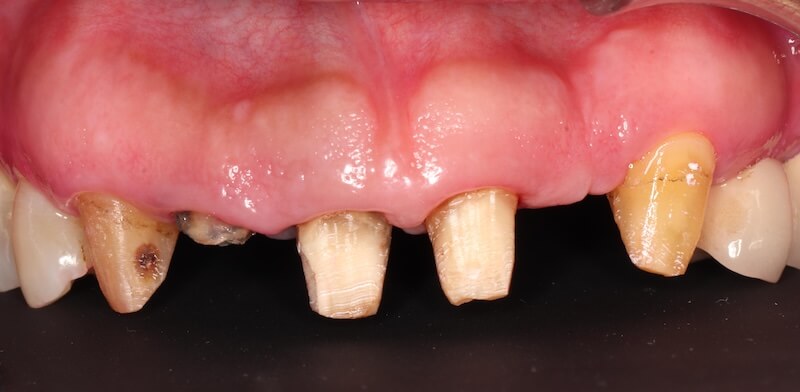

另一個問題是前面六顆已經不密合的假牙,要拆掉才能解決這個會加重牙周病的因素。計畫要把前面的假牙拆除後,先製作一套假牙邊緣比較淺的臨時假牙,初步解決假牙邊緣侵犯牙齒生物寬度的問題。

拆除舊假牙:釐清殘留牙根與齒質狀況

拆除舊假牙換上臨時假牙之後,開始進入牙周病的療程。我們會先將治療前口內狀況完整記錄,詳細分析每一顆牙齒的牙周狀況。